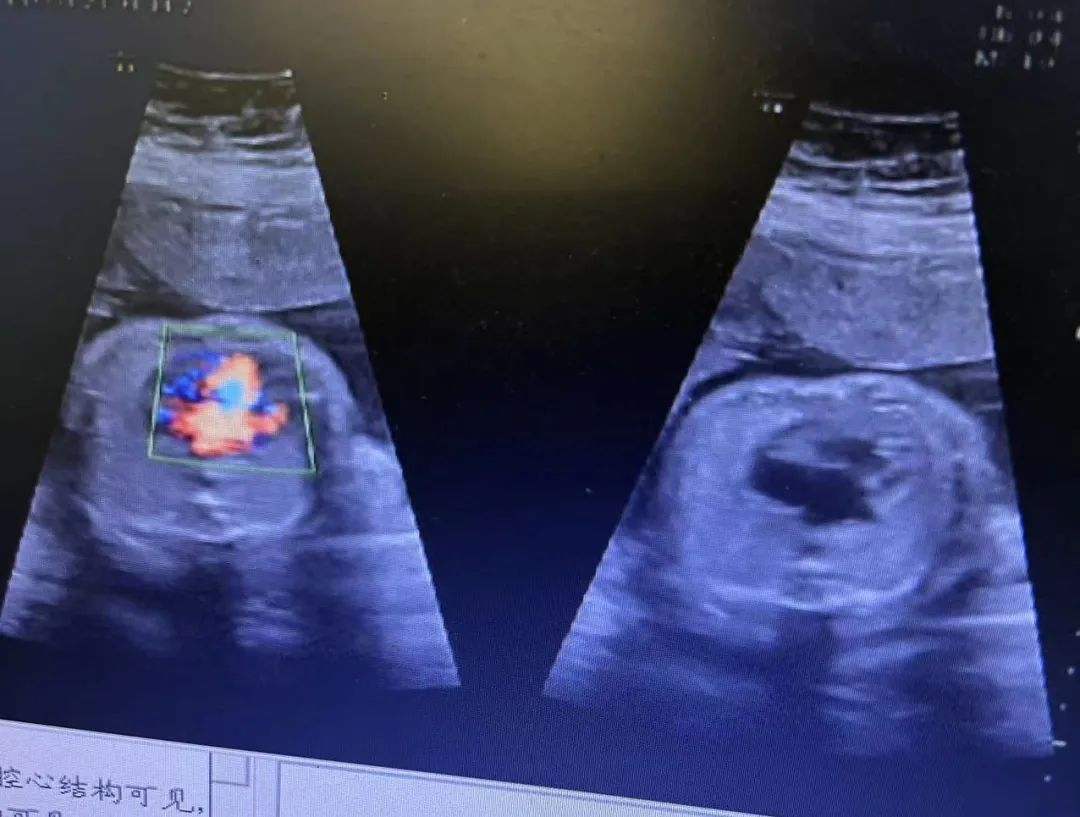

近日,我院超聲科醫(yī)生在給孕中期孕媽做四維彩超檢查時(shí),發(fā)現(xiàn)胎兒查出異常,孕媽想留下這個(gè)寶寶,陷入了兩難。

武漢的劉女士(化名),前幾個(gè)月剛懷上寶寶,全家都特別高興。懷孕23周+時(shí),劉女士在家人的陪伴下來到武漢仁愛醫(yī)院超聲科做了四維彩超檢查,當(dāng)醫(yī)生拿出檢查報(bào)告的時(shí)候,劉女士卻當(dāng)場(chǎng)傻眼了,原來,在四維彩超的報(bào)告里,診斷出了胎兒右肺囊性腺瘤樣病變,她的心頓時(shí)揪了起來!

劉女士看到檢查結(jié)果后,擔(dān)心該病變會(huì)影響腹中寶寶的健康,考慮是否應(yīng)該終止妊娠。隨即,武漢仁愛醫(yī)院超聲科王娟主任為劉女士耐心地解釋:“先天性肺囊腺瘤是一種肺組織錯(cuò)構(gòu)畸形,先天性肺囊腺瘤畸形病例約70%的腫塊大小較穩(wěn)定;約20%腫塊產(chǎn)前明顯縮小或消失;僅10%腫塊是進(jìn)行性增大。單純的先天性肺囊腺瘤(CCAM)無水腫的胎兒可以密切隨訪,在28周前接受連續(xù)超聲復(fù)查,CVR<1.6,一般超聲動(dòng)態(tài)監(jiān)測(cè)2~4周監(jiān)測(cè)一次,而對(duì)于CVR≥1.6的需要在28周前每周1-2次的超聲監(jiān)測(cè),防止出現(xiàn)胎兒水腫,直到分娩。”